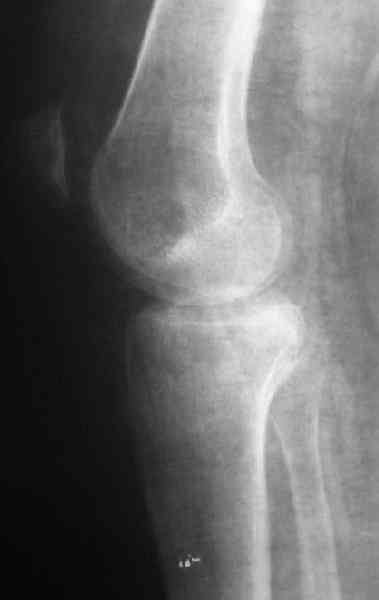

[Ortho] Застарелый перелом 41С3

Недавно поступила больная через 1,5- 2 месяца.